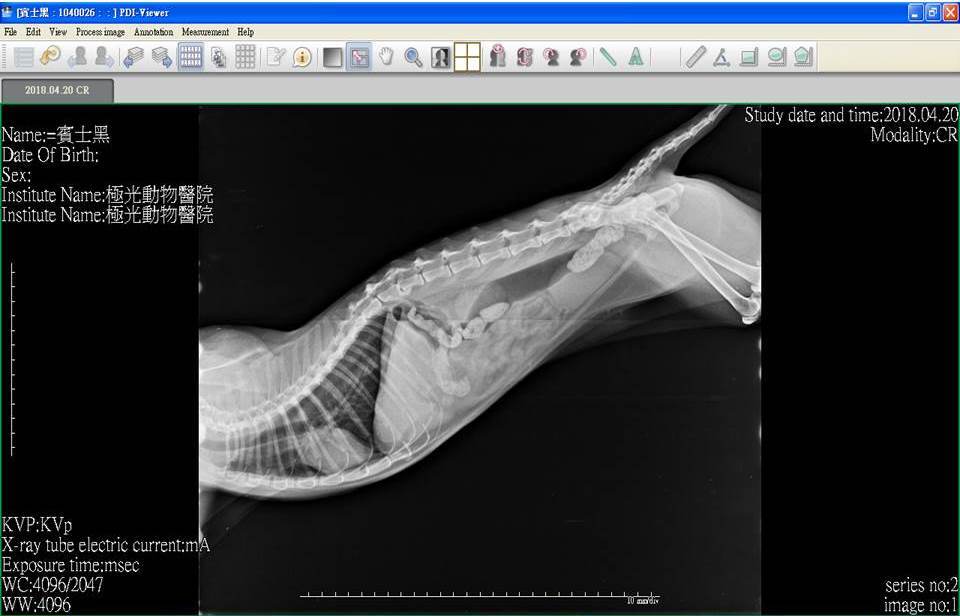

主題: 患有腎衰口炎胰臟炎的麵滷 申請者姓名: 臺北市支持流浪貓絕育計劃協會 花色: 申請日期: 2018-05-08 17:24:45 申請者部落格: 申請者臉書網址: http://admin.tnrtw.org/hospice_add.php 所在縣市/合作醫院: 台北市/極光動物醫院 治療費用: 3600元 需求人數: 8人 已結案 (2024-06-01 13:12:24) 報名人員: 劉小賢(已付款)、林小豬 x2(已付款)、Ed Tsai x5(已付款)、 候補人員: 動物病情說明: 麵滷患有腎衰、嚴重口炎、胰臟炎,這些病症都會讓牠食慾較差,除了吃藥打皮下注射,協會照護員每日都會灌食以維持牠的體力,並每週定期看診做詳細檢查,近日牠因食慾下降更多,精神不好,協會立即安排帶牠就醫,做了血檢及x光,牠的口炎情況變得更嚴重,醫生開了藥希望可以讓麵滷口炎情況好轉,就能恢復些食慾。 動物近況說明: 每週回診、服藥、每日皮下輸液、灌食、給自煮鮮食,希望可以讓牠病情穩定。